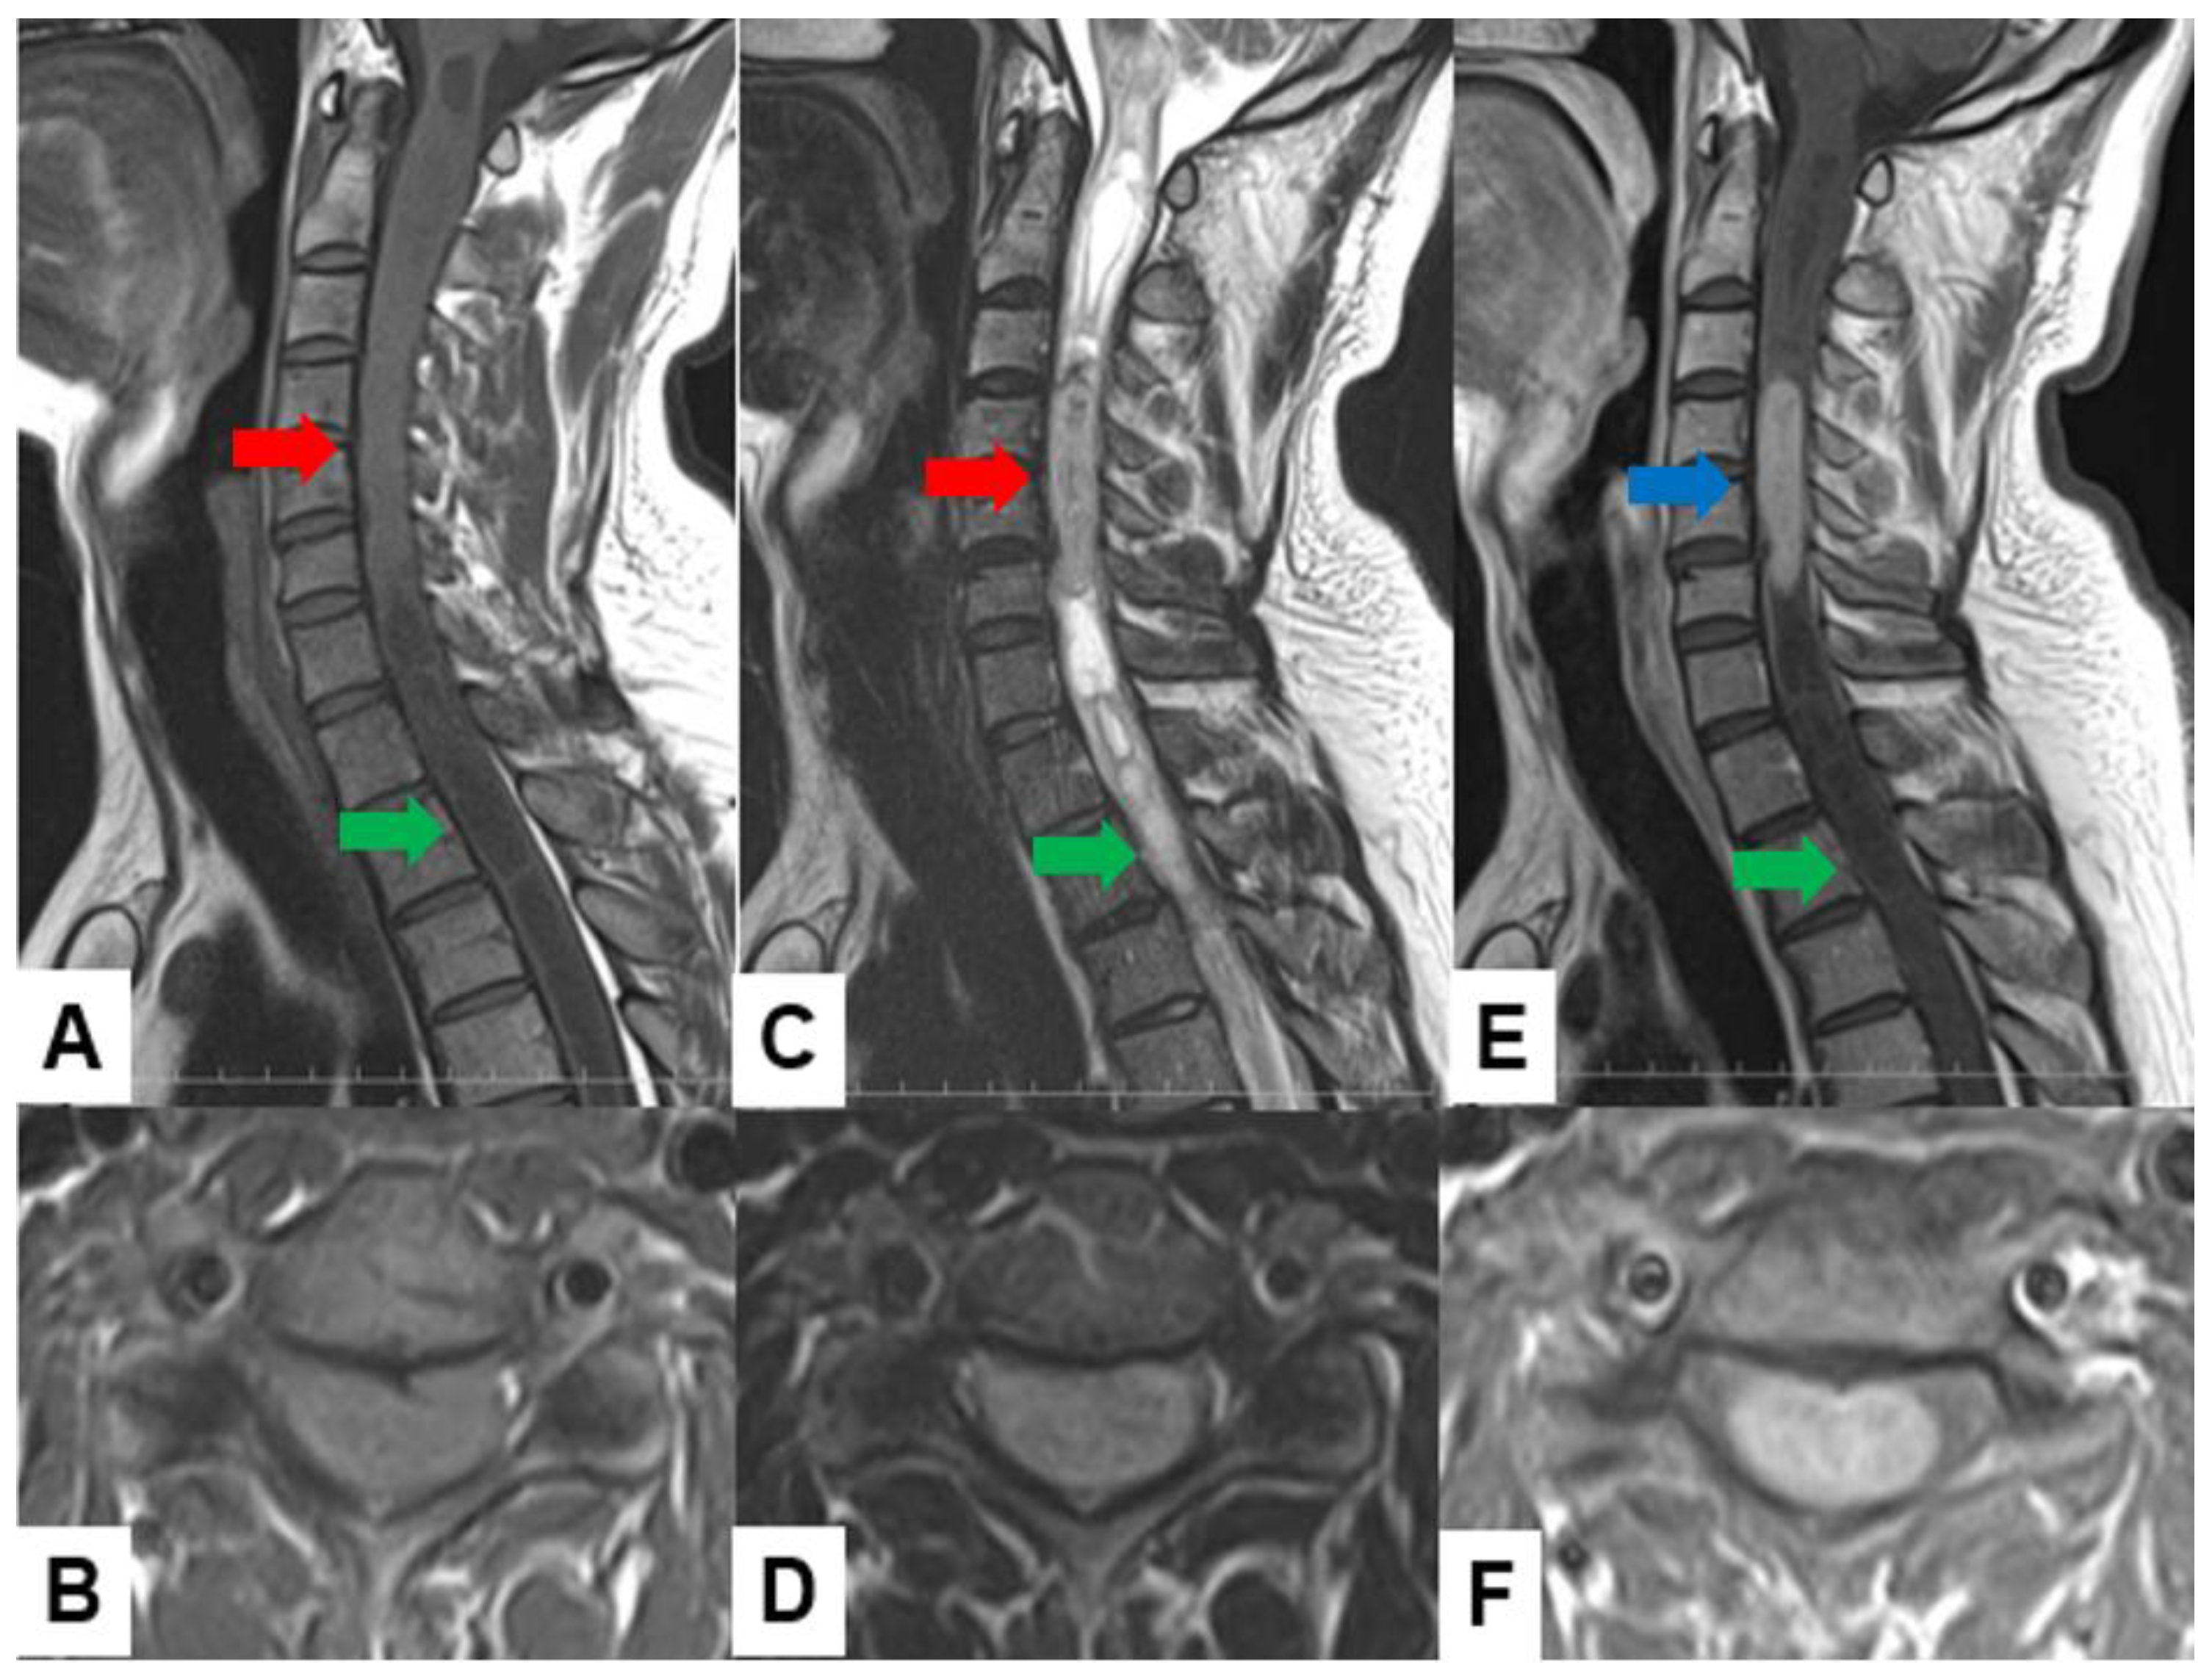

Meningiomas usually indicate isointensity in both T1- and T2-weighted MR imaging and are enhanced homogeneously (Figure 3) [35]. Meningiomas are sometimes calcified and are recognized in CT (Figure 4). The key points of a differential diagnosis of meningioma and schwannoma are in Table 4.

Figure 3.

Forty-two F, spinal meningioma. (A) T1-weighted midsagittal image, (B) T2-weighted midsagittal image, and (C) enhanced T1-weighted midsagittal image. (D) CT. Red arrows indicate tumor and blue arrow shows tumor enhancement. Yellow arrow shows dural tail sign and black arrow indicates tumor ossification.

Figure 4.

Sixty-eight F, spinal meningioma. (A) Enhanced T1-weighted midsagittal image, (B) enhanced T1-weighted axial image at T7/8, (C) T2-weighted midsagittal image, (D) T2-weighted axial image at T7/8, (E) midsagittal reconstruction CT, and (F) axial CT at T7/8. Red arrows indicate tumor, and blue arrows show tumor enhancement. The tumor is calcified (white arrows).